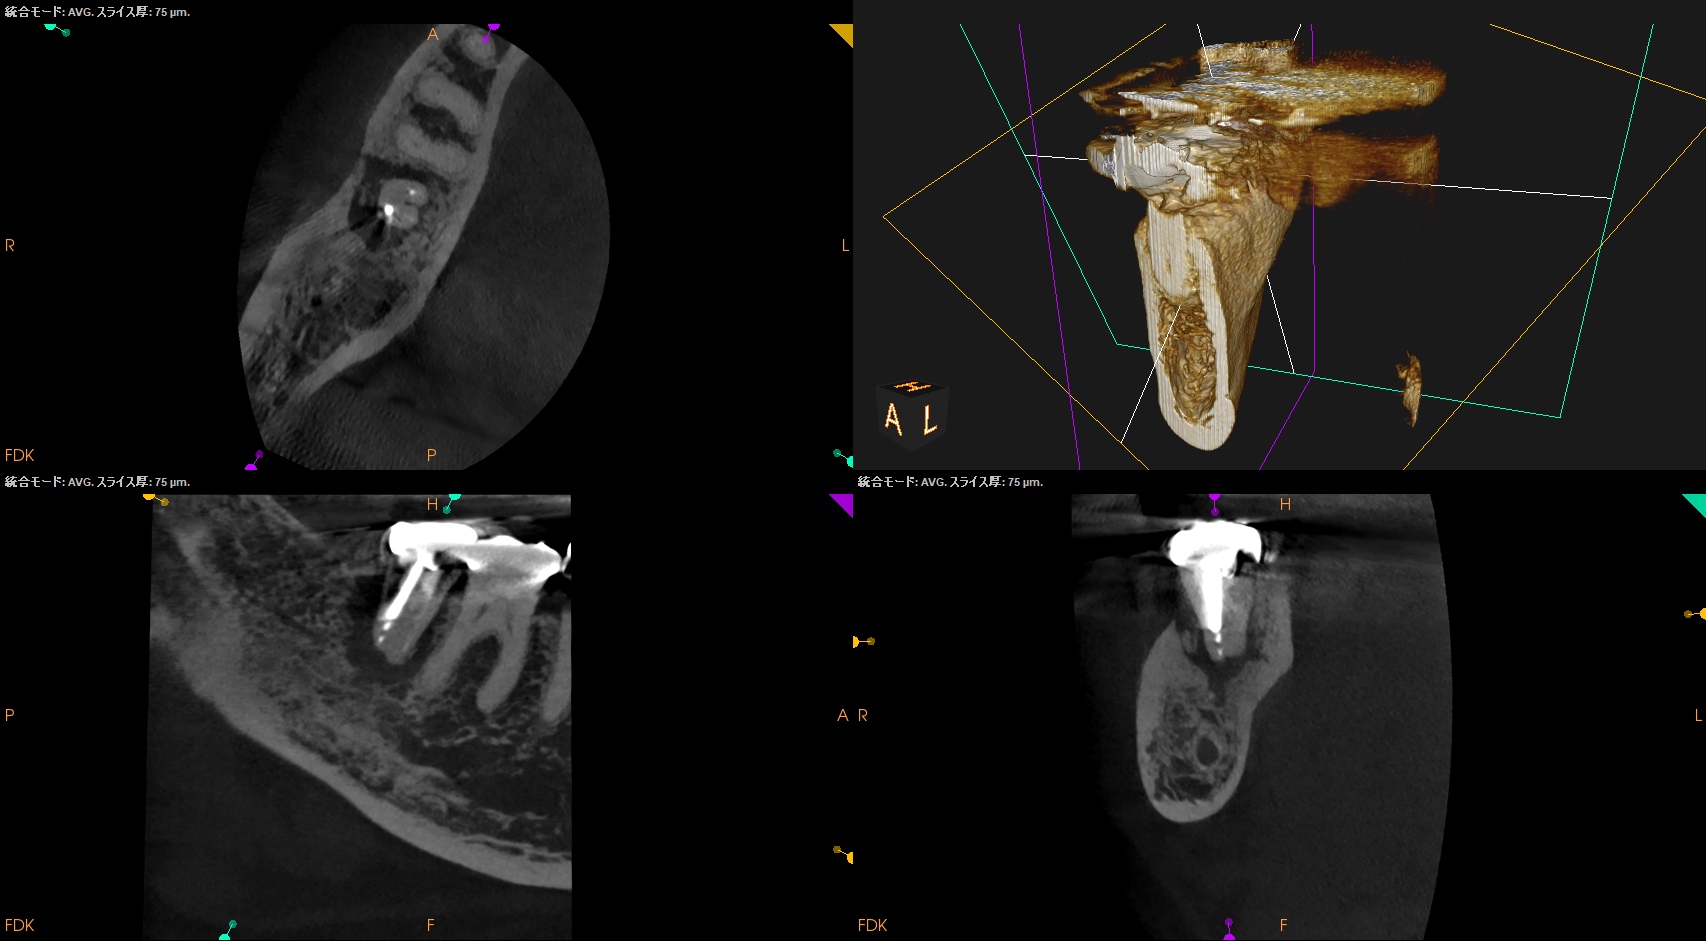

PA, CBCTを撮影した。

ML

MB

D

問題はないだろう。

この歯牙の根尖部の歯槽骨が回復するかどうか?は時間が解決する。

そしてこれこそ、

エンド→ペリオなのか、ペリオ→エンドなのか、ペリオ+エンドの合併症なのか?の判断が迫られる難しい治療であろう。